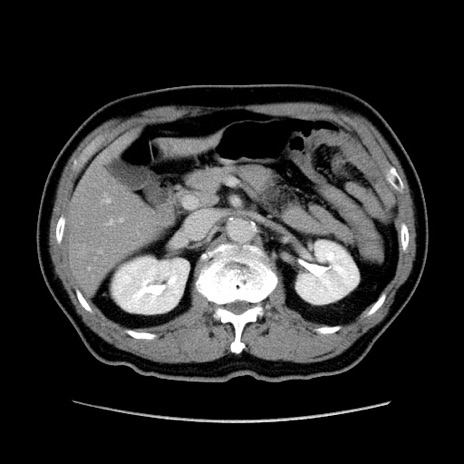

症例34(横断像)

【症例】60歳代 男性

【主訴】右鼠径部膨隆

【現病歴】1年程前より右鼠径部膨隆あり。自己にて還納可能だったため放置していた。3時間前より右鼠径部の脱出を認め、還納困難となり受診。

【身体所見】右鼠径部に小児頭大の膨隆あり。弾性硬であり、用手還納は困難。左鼠径部にも膨隆を認める。脱出はなし。